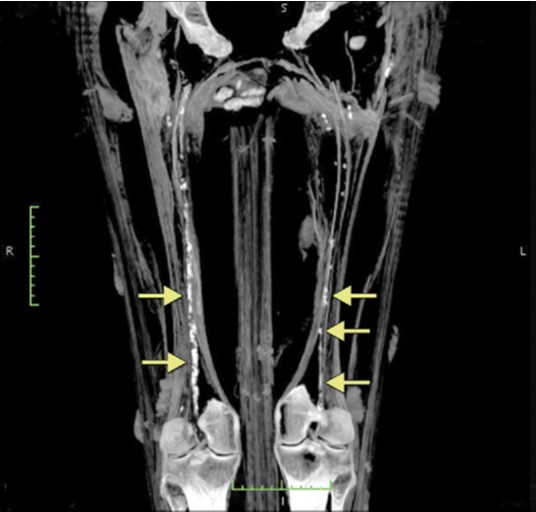

Mentre se sono coinvolti i vasi delle gambe (“dolore attraverso le cosce e le gambe tremano”) il papiro suggerisce una miscela di latte fresco, assenzio e natron, da far bollire e far bere al paziente sempre per quattro giorni. Da notare che secondo alcuni studiosi questo passaggio si riferirebbe alle vene varicose.